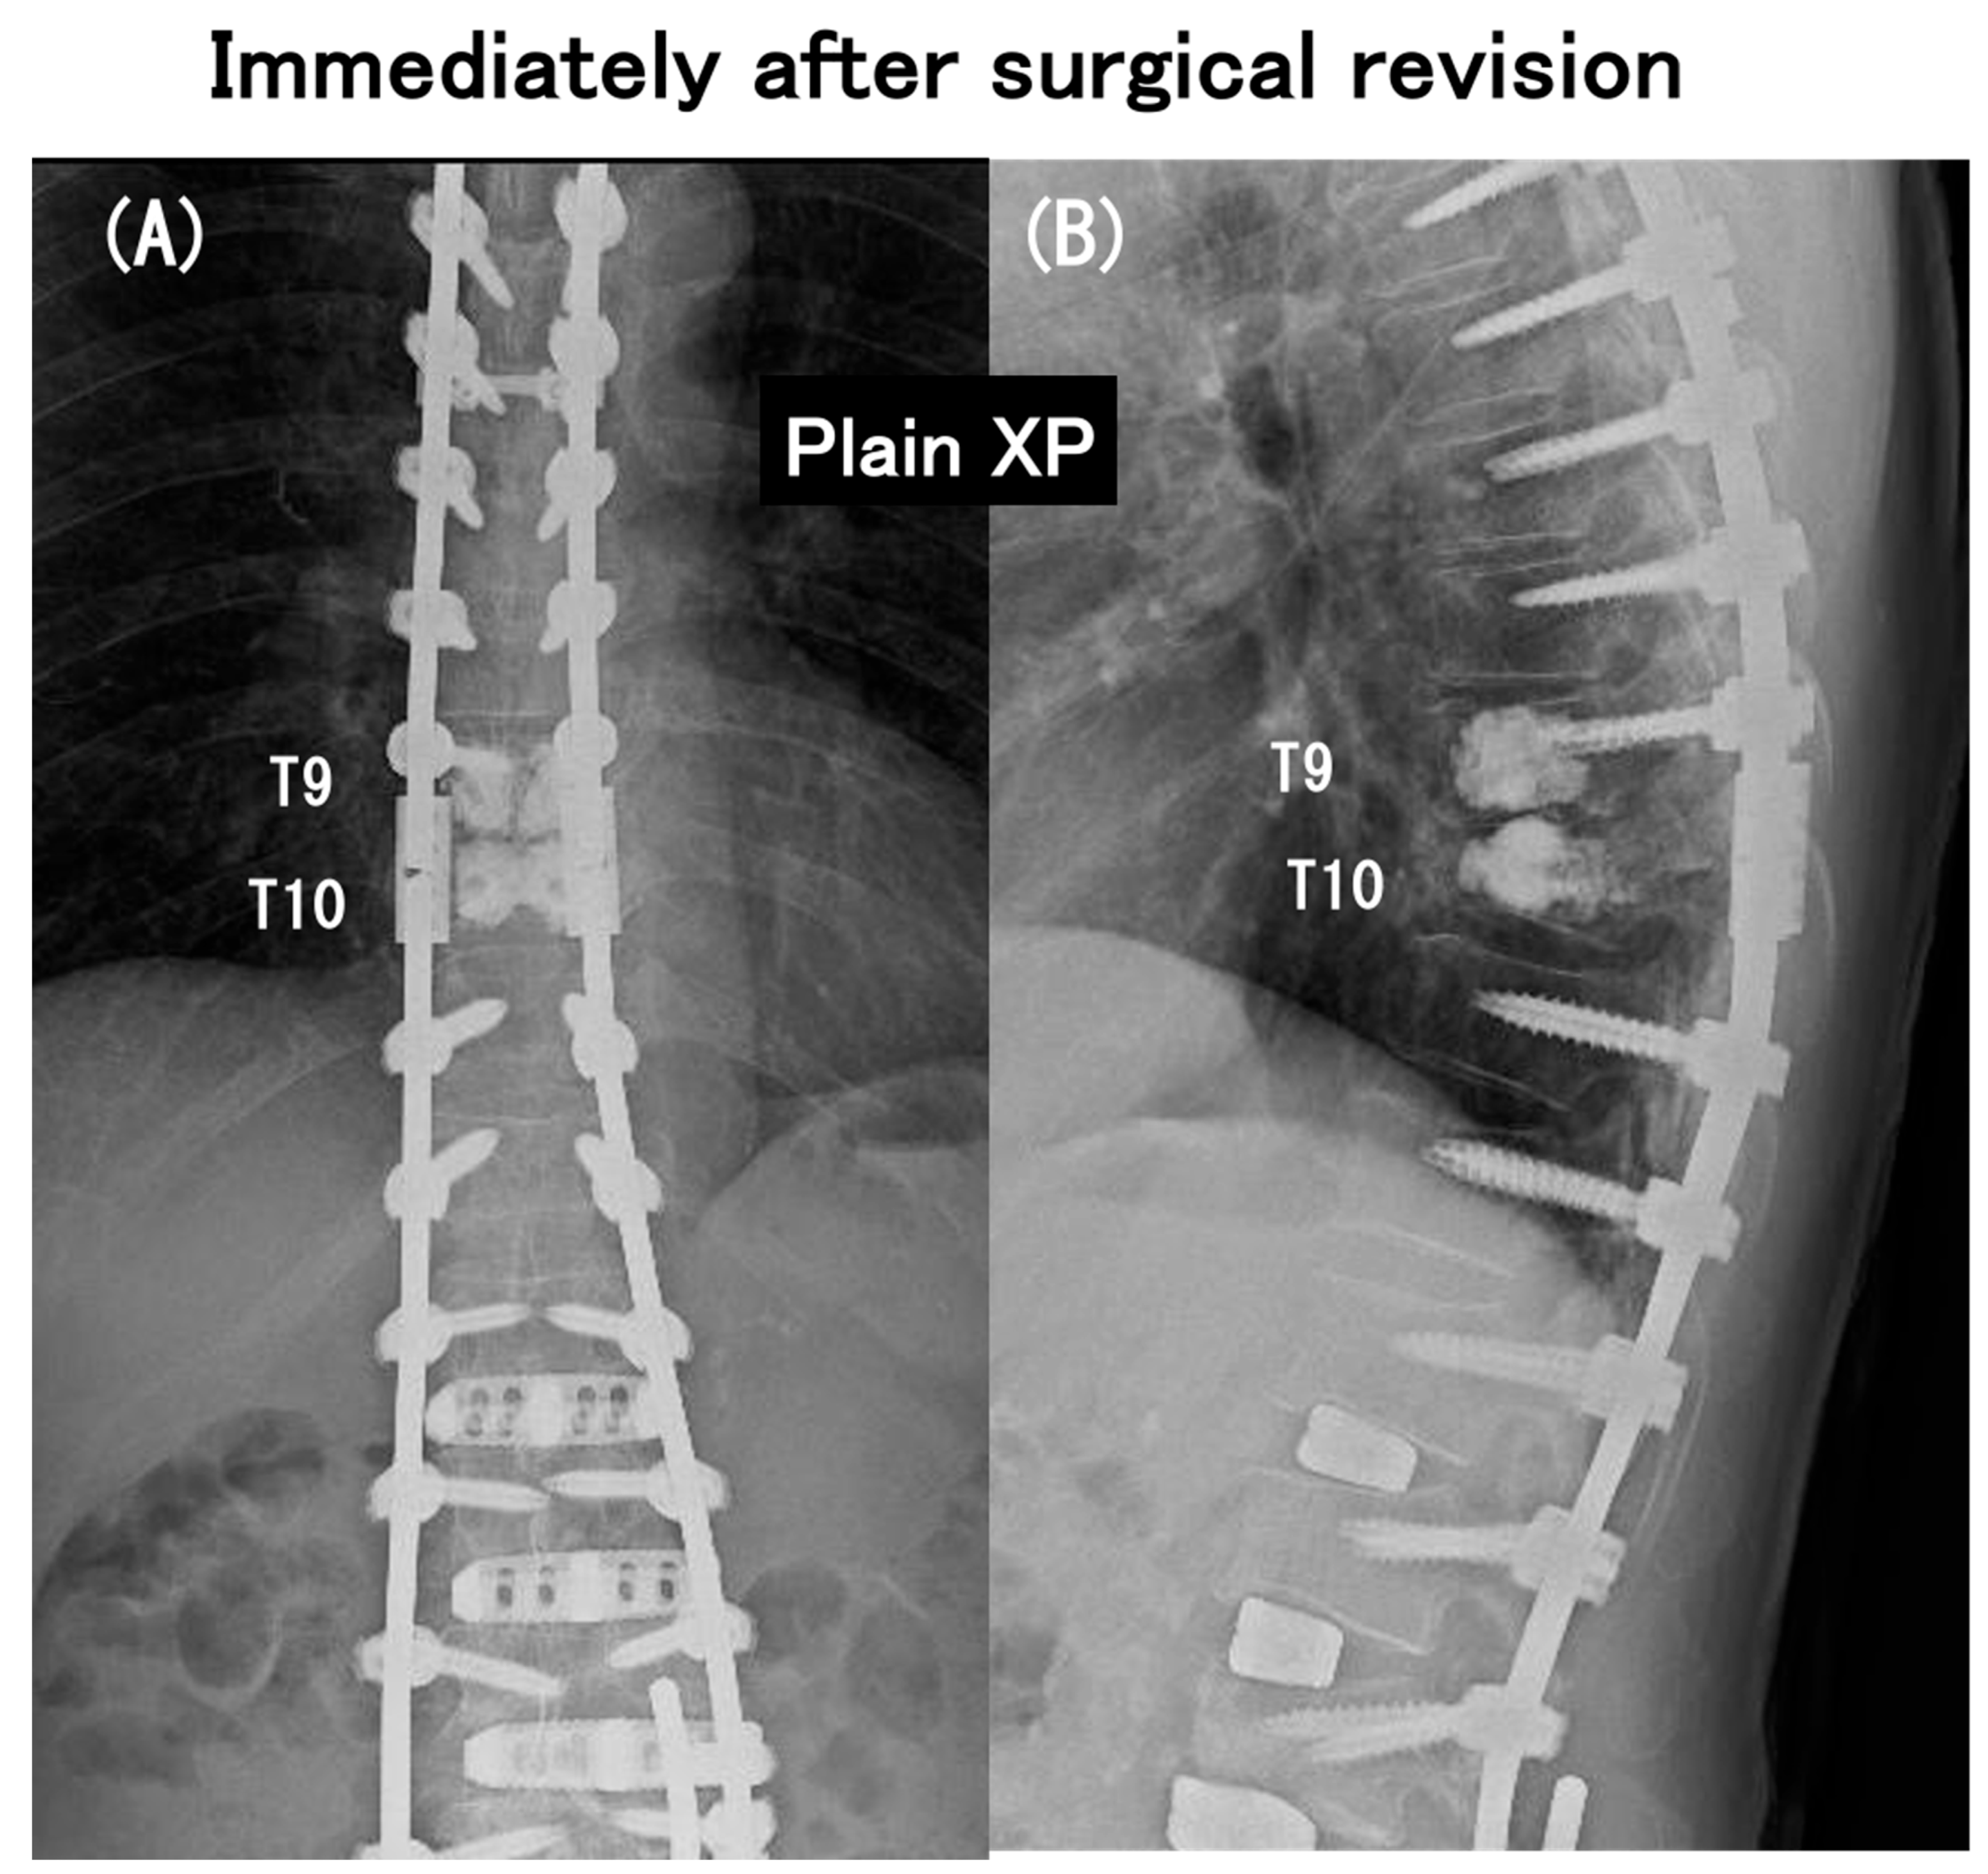

3.6. Case Presentation

- Case no. 6

- 2.

- Case no. 4